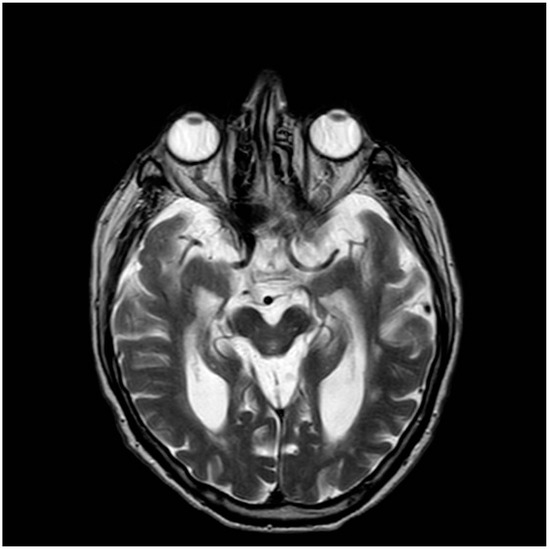

- Morning glory sign: This refers to the appearance of the tonsils on sagittal MRI images. In individuals with PSP, the cerebellar tonsils often appear elongated and point downward, resembling the shape of a morning glory flower (Figure 2) [25].

Figure 2. Axial MRI T2 scan demonstrating characteristic morning glory sign in PSP.